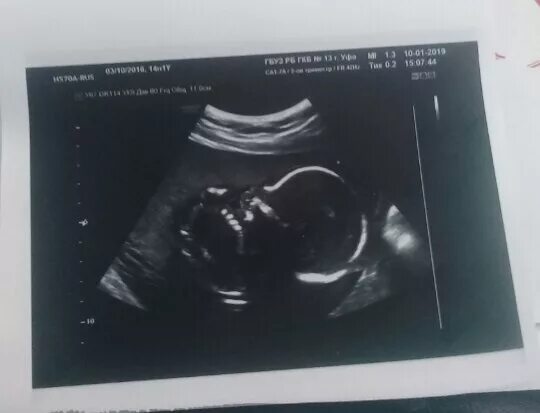

Скрининг 10